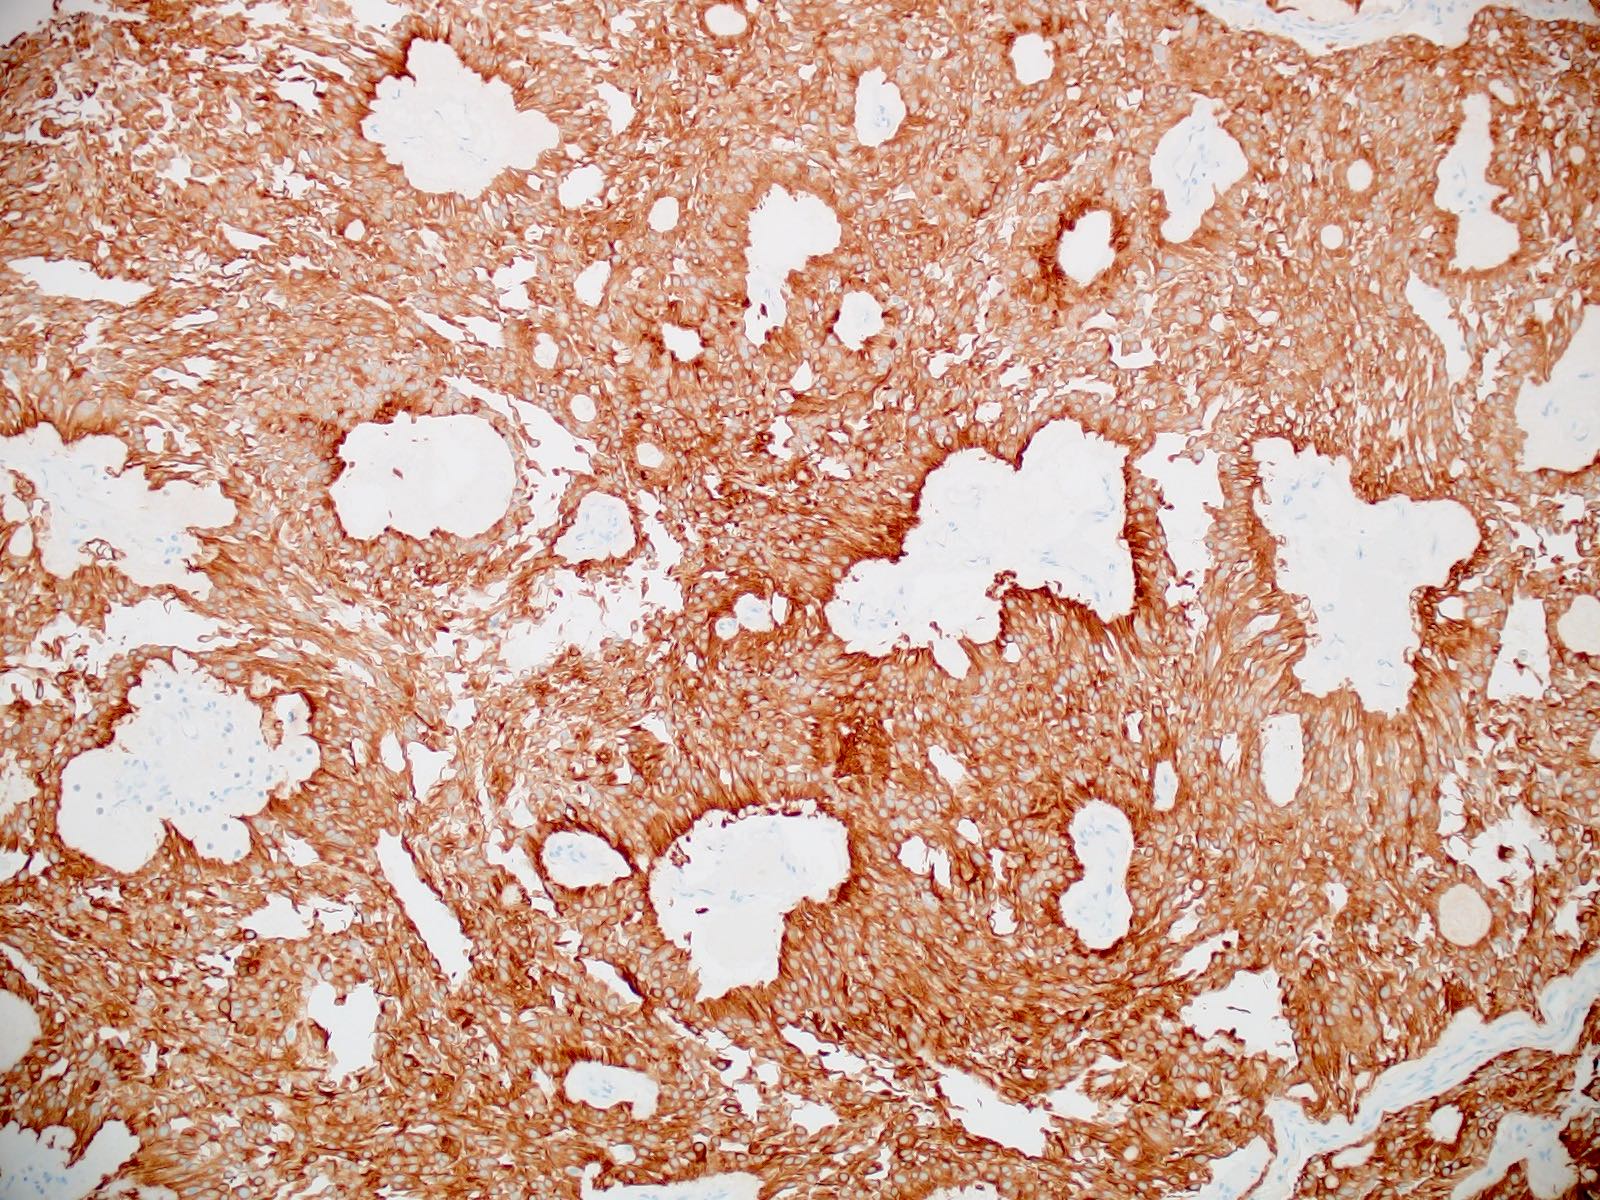

- Immunoreactive for glial fibrillary acidic protein (GFAP)

Positive stains

- Positive for GFAP (diffuse expression of GFAP distinguishes myxopapillary ependymomas from other tumors in the differential diagnosis, such as metastatic carcinomas, chordomas, paragangliomas, myxoid chondrosarcomas, schwannomas, etc.)

- Positivity for S100 is typical; CD99, vimentin and CD56 positivity is seen frequently

- Positivity for cyclooxygenase 2 (COX2) is seen in the majority of cases (60%) (Neuropathology 2006;26:422)

- Often positive for keratin AE1 / AE3 cocktail (Appl Immunohistochem Mol Morphol 2013;21:485, Appl Immunohistochem Mol Morphol 2000;8:25)

Microscopic (histologic) images